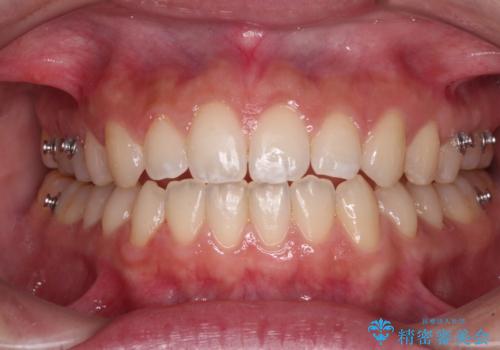

【モニター】隙間だらけの前歯を治したい インビザラインによる矯正治療

- 上下前歯の隙間と咬み合わない前歯を気にして来院された患者様です。

開咬の治療は、前歯を閉じるように動かすとともに、上下臼歯を圧下(骨内にめり込ませる)させることで進めて行きます。

インビザラインは臼歯の圧下を効果的に行えるため、インビザラインを用いて矯正治療を行うこととしました。

開咬とすきっ歯は、舌の突出癖改善が必須となるため、トレーニングを徹底的に行うよう指示しました。

仕上がりとしては、もう少し上下前歯を接触させたかったのですが、ここまで改善されたことで患者様は大変満足され、治療を終えることとなりました。